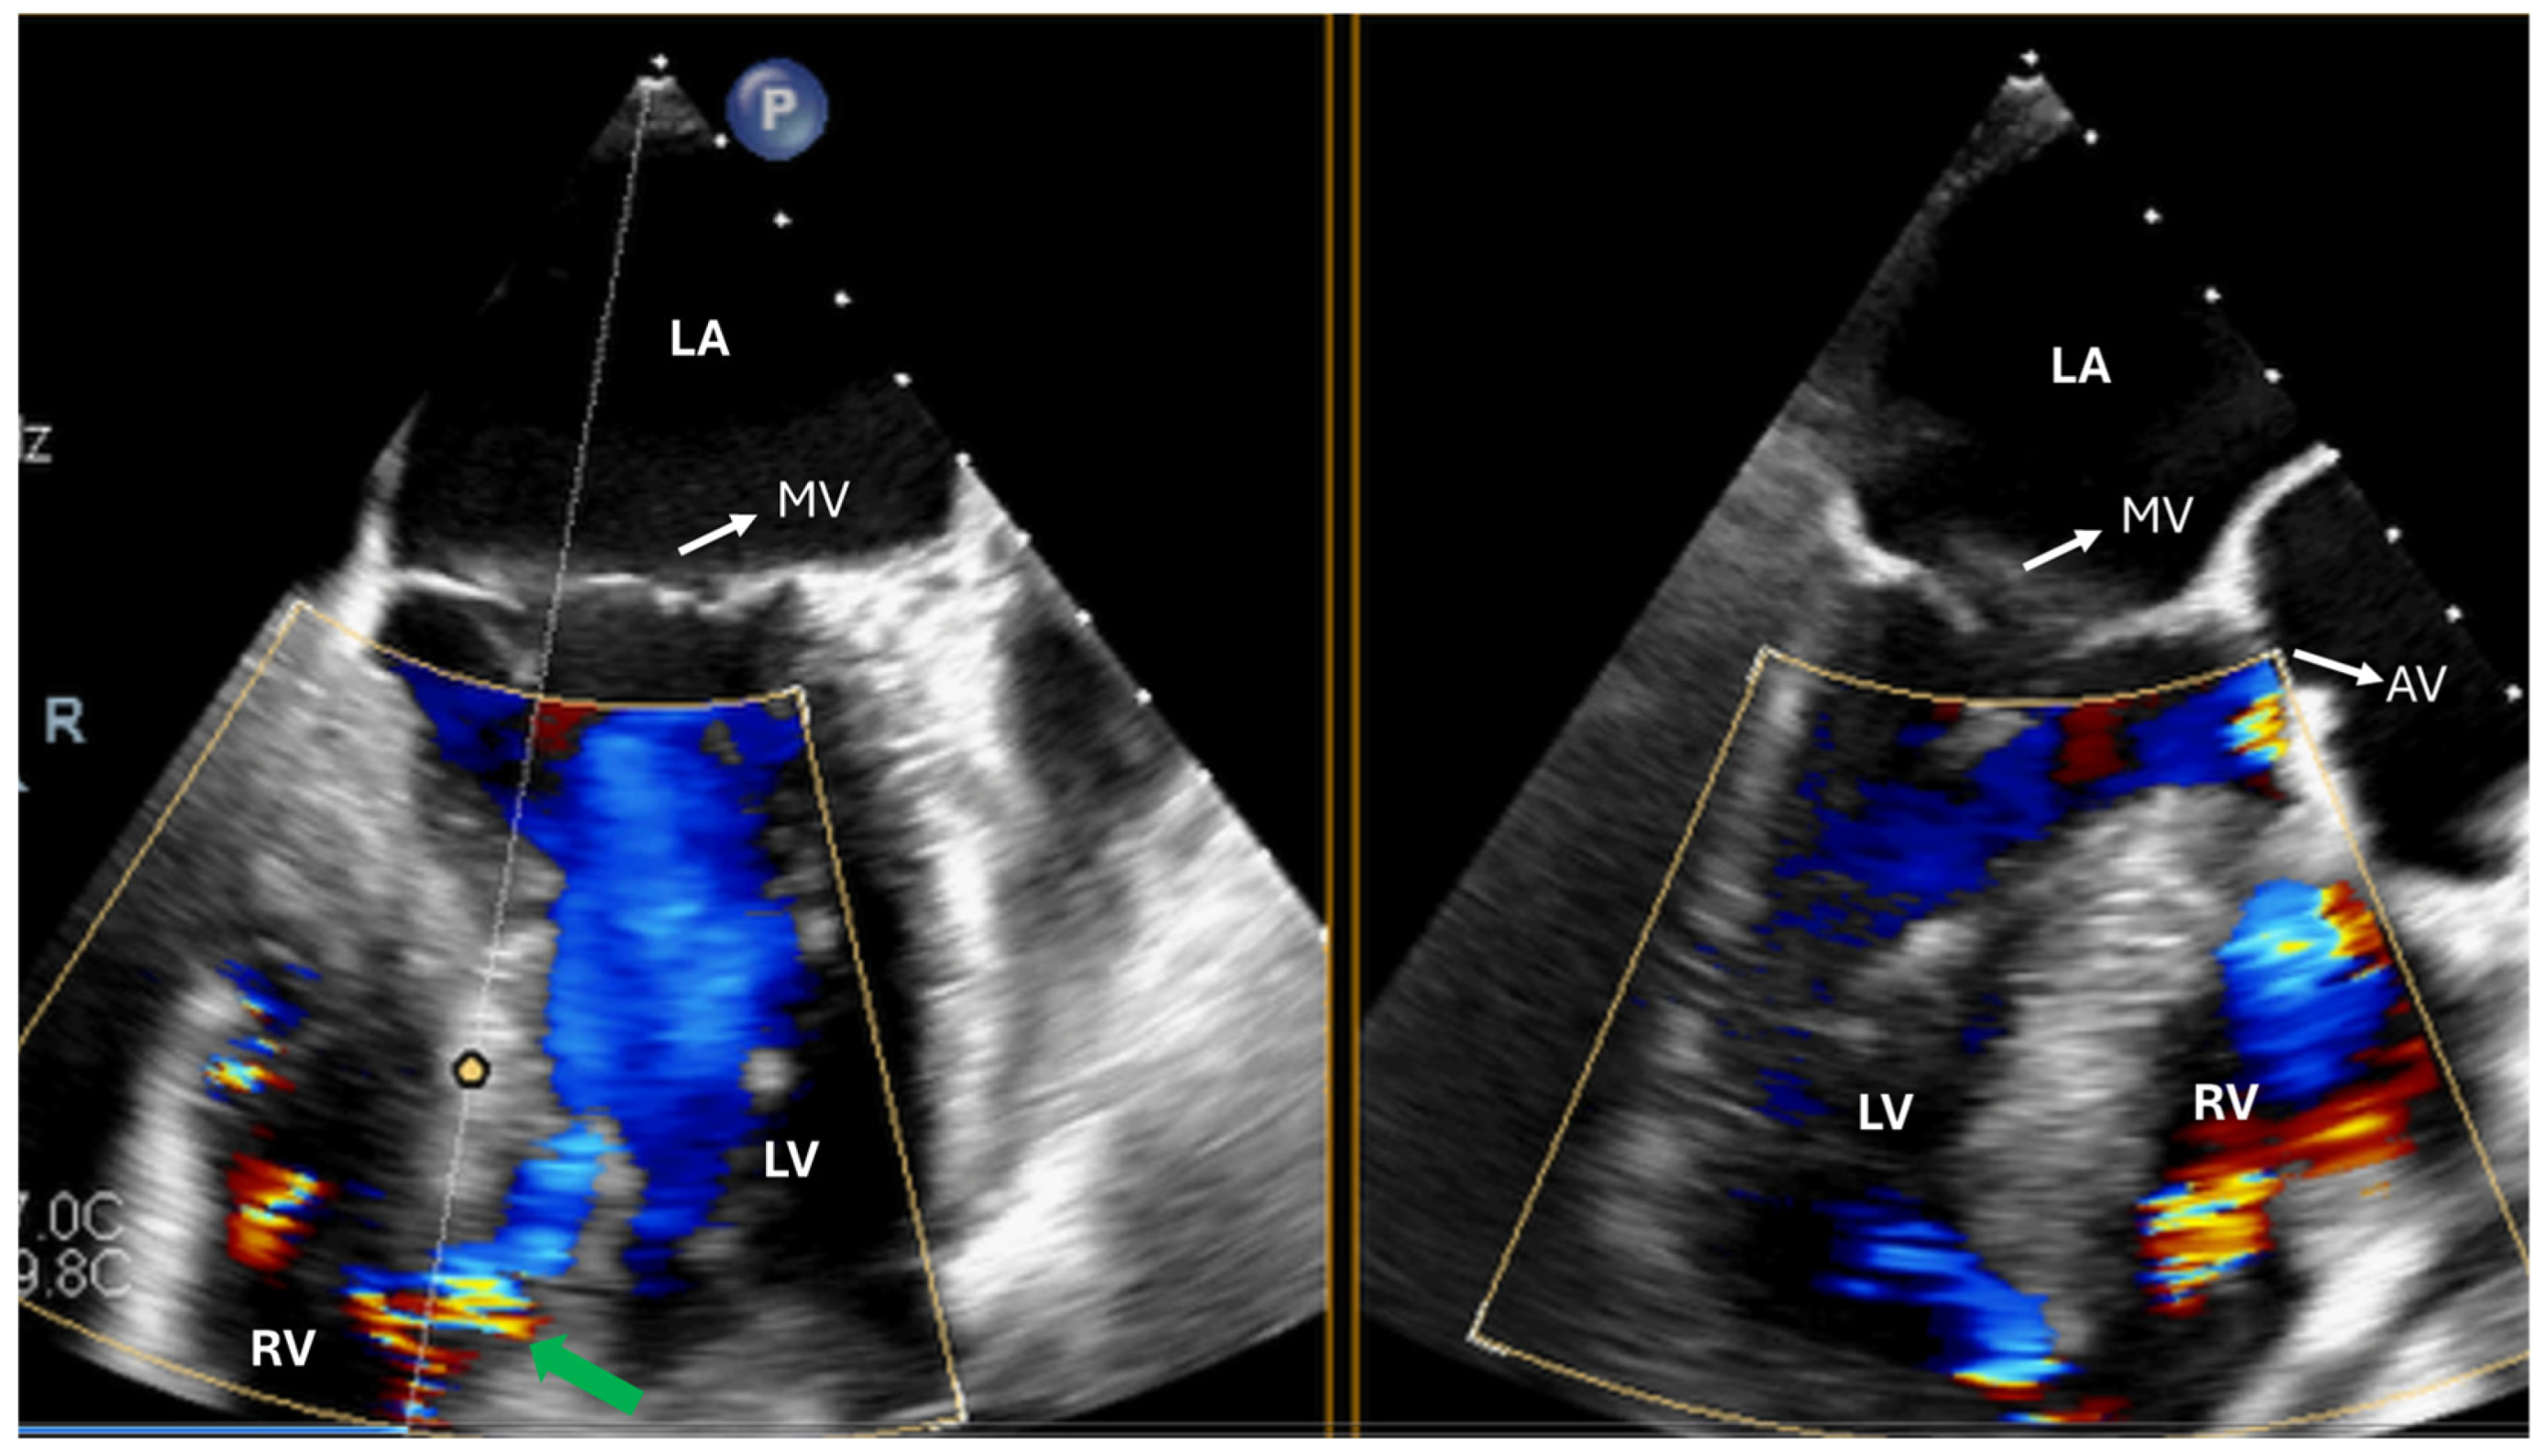

4. Tricuspid Valve Disease

| TV repair | Describe TR mechanism Describe TV anatomy Measure TV annulus | Exclude iatrogenic TV stenosis |